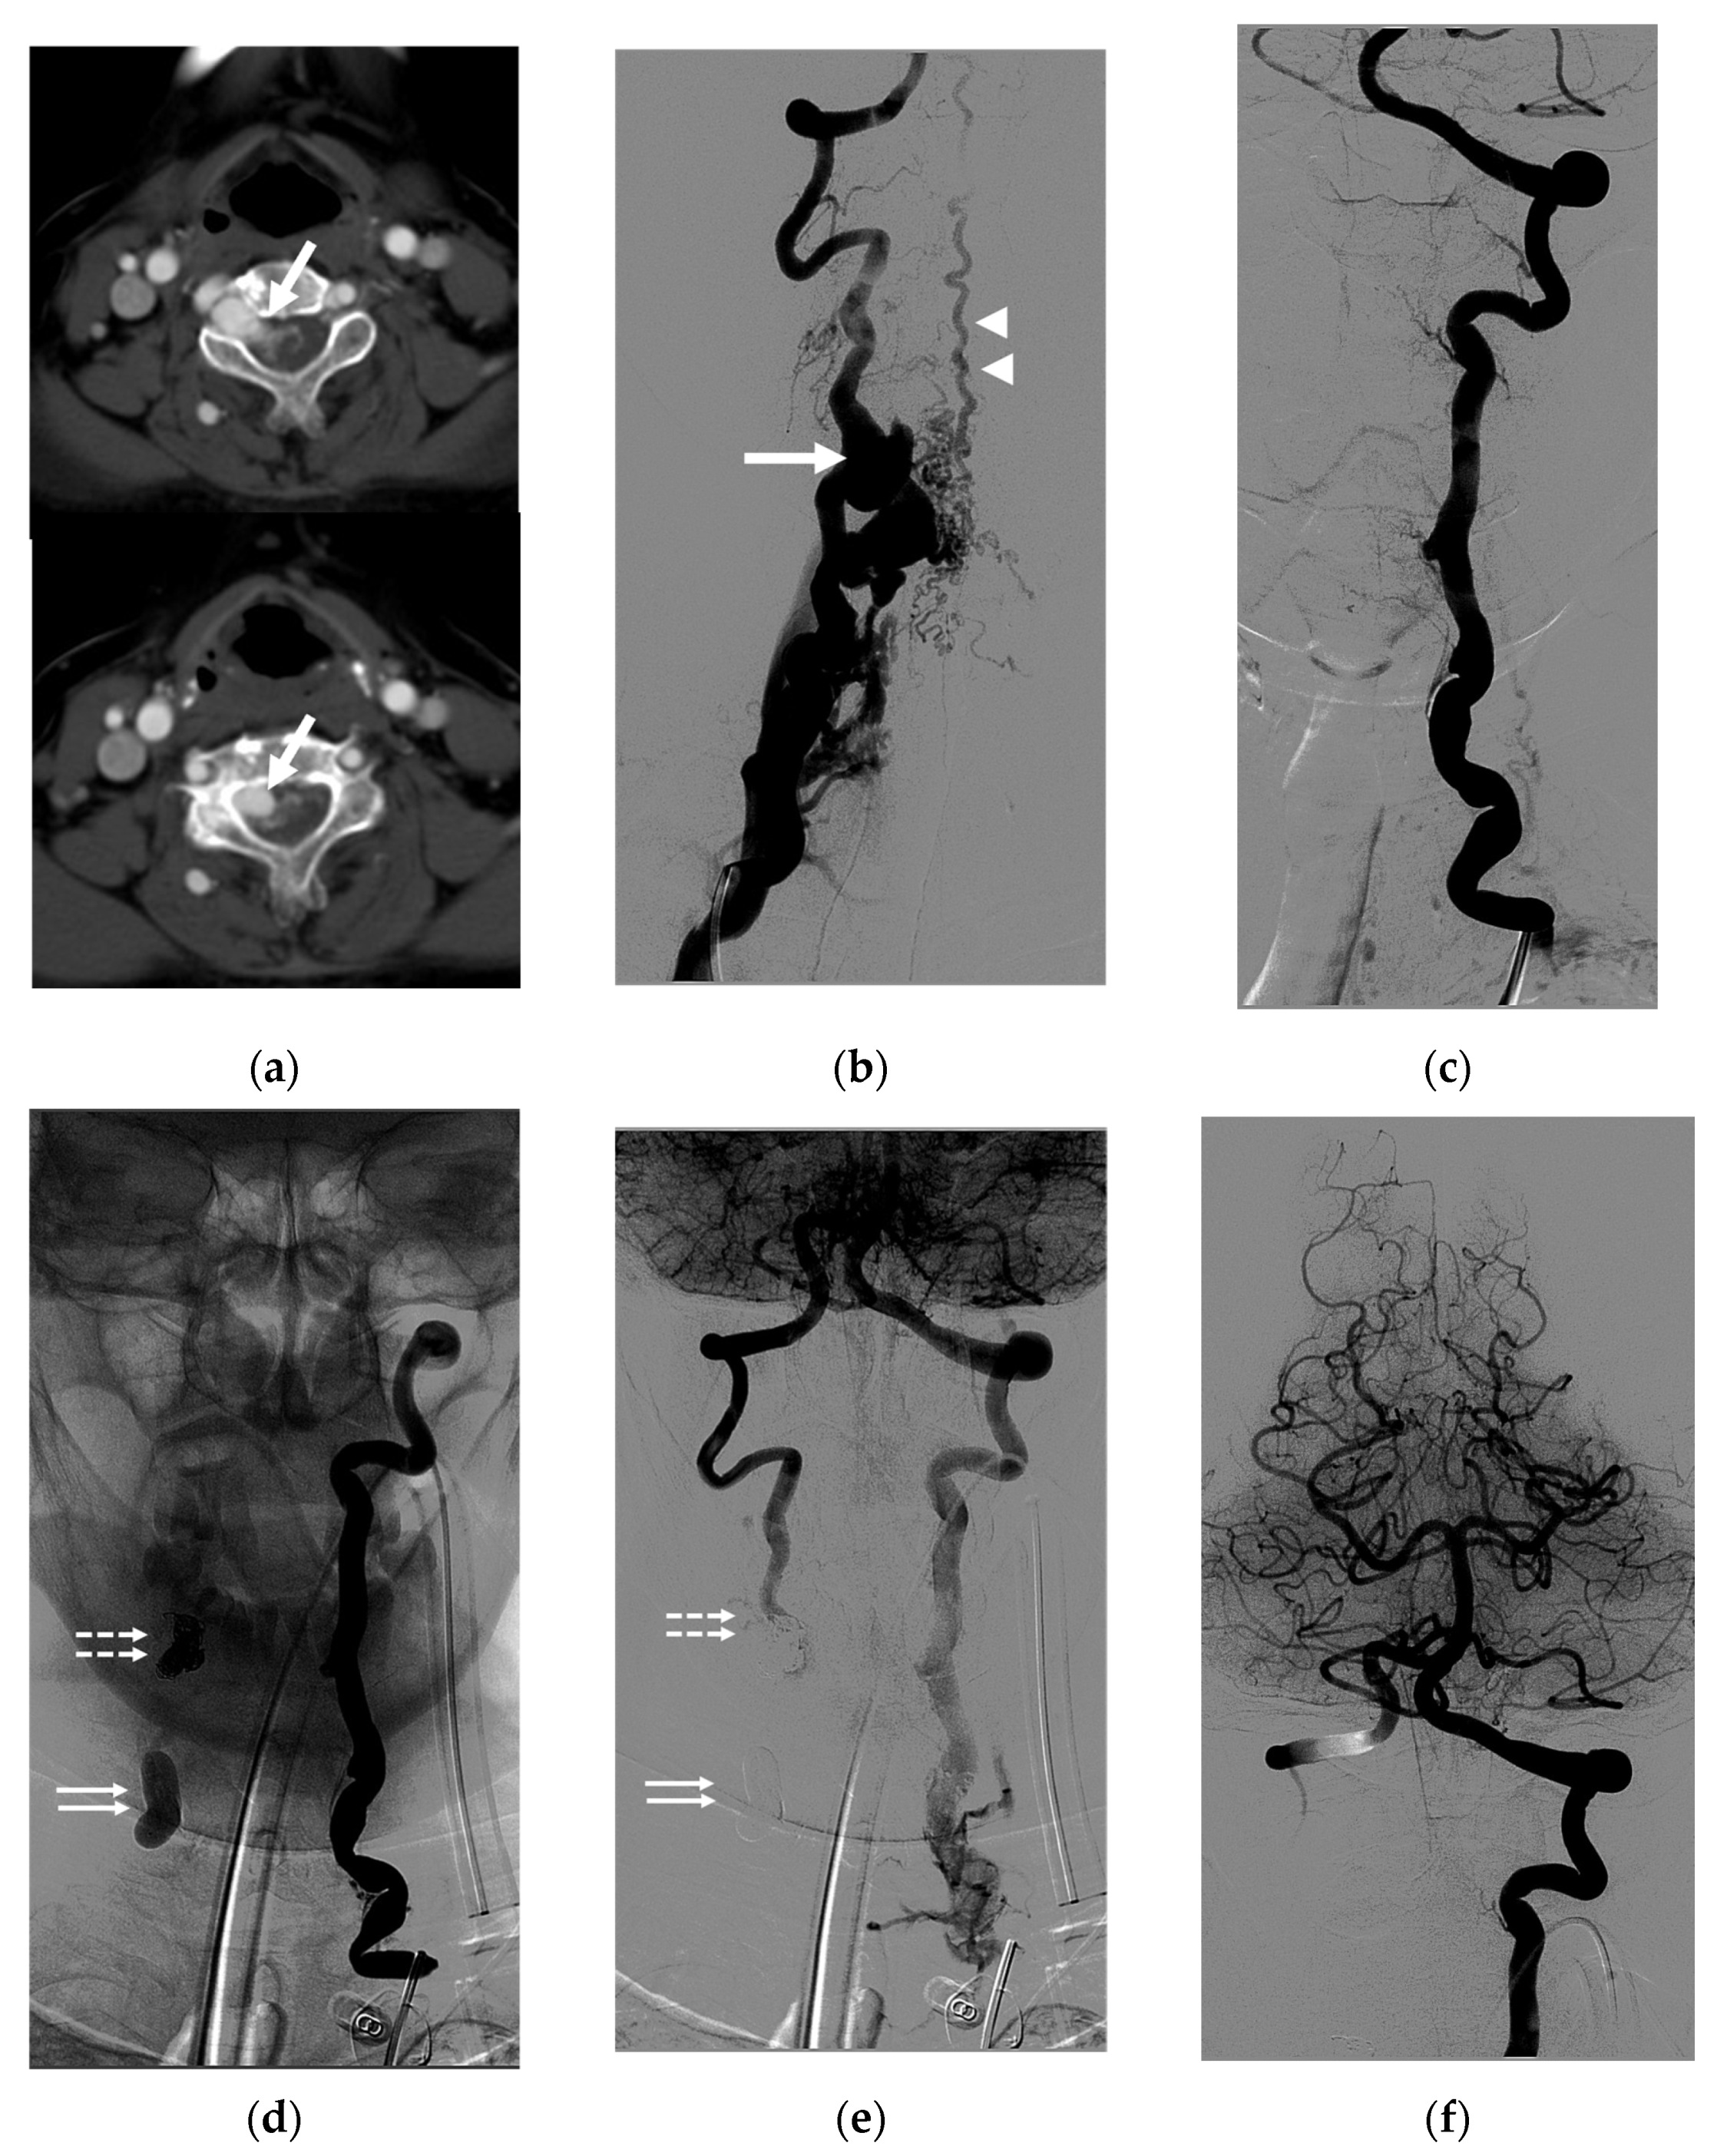

| 13 | M | 57 | Neck mass; right arm weakness | Traffic accident | T | Radicular vein; IJV with venous pouch | Y | C | O | Improved | None |

| 14 | M | 36 | Bleeding in epidural space after surgery | Traffic accident | T | VVP with ruptured venous pouch in epidural space | N | B | O | Improved | None |